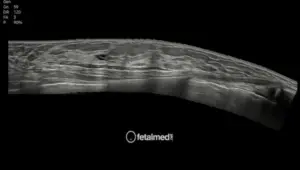

• Artérias uterinas — rastreio precoce de risco de pré-eclâmpsia